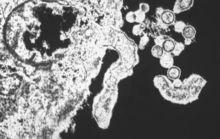

漢坦病毒歸屬布尼亞病毒科,是一種有包膜分節段的負鏈RNA病毒,基因組包括L、M、S 3個片段,分別編碼L聚合酶蛋白、G1和G2糖蛋白、核蛋白。漢坦病毒包括引起腎綜合徵出血熱(HFRS)的漢灘病毒(Hantaan virus,HTNV)、漢城病毒(Seoul virus,SEOV)、普馬拉病毒(Puumala virus,PUUV)、多不拉伐病毒(Dobrava virus,DOBV),引起漢坦病毒肺綜合徵(HPS)的無名病毒(Sin Nombre virus,SNV)、紐約病毒(New York virus,NYV)、污黑小河溝病毒(Black Creek Canal virus,BCCNV)、牛軛湖病毒(Bayou virus,BAYV)、安第斯病毒(Andes virus,ANV)以及與人類疾病關係尚不清楚的一組病毒,如希望山病毒(Prospect Hill virus,PHV)、泰國病毒(Thailand virus,THAIV)、圖拉病毒(Tula virus,TULV)、索托帕拉雅病毒(Thottapalayam virus,TPMV)、哈巴羅夫斯基病毒(Khabarovsk virus,KBRV)、El Moro Canyon病毒(ELMCV)、Rio Segundo病毒(RIOSV)、島景病毒(Isla vista virus,ISLAV)、Muleshoe病毒(MULEV)、Bloodland lake病毒(BLLLV)、Rio Mamore病毒(RMV)、Topografov病毒(TOPV)等。近年來隨著新技術的套用和新型病毒的發現,漢坦病毒及其相關疾病的研究得以飛速發展。1998年3月5~7日,第四屆國際HFRS和漢坦病毒會議在美國亞特蘭大市召開,與會的世界各國學者和專家交流了這一領域的最新研究方法和研究成果。